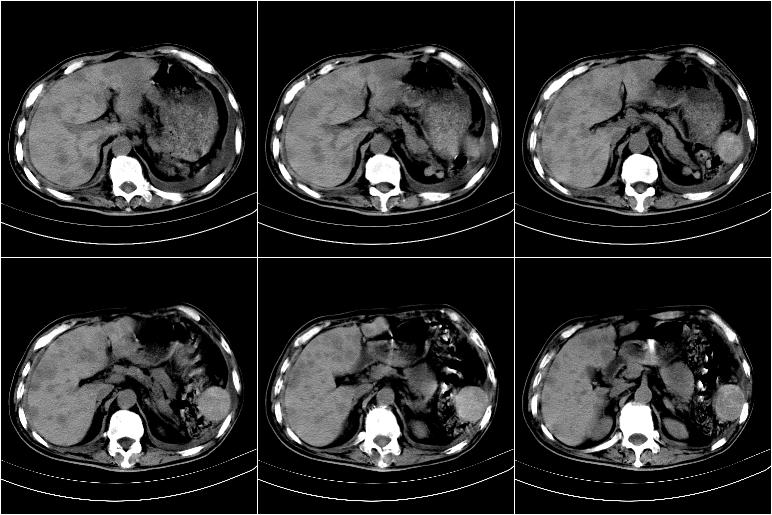

以下是引用边生丽在2009-8-17 11:43:00的发言:[br][br] [br] 右肺中心型癌伴右肺下叶不张、双肺转移并癌性淋巴管炎、心包和双侧胸腔积淮(转移?)、脑转移、肝转移、多骨(颅骨、椎骨)转移。 [br] [br]

以下是引用奥特之父在2009-4-20 19:58:00的发言:[br]支持胰腺癌并转移性病变。

以下是引用随光逐影在2009-8-17 14:09:00的发言:[br]支持 右肺中央型癌伴右肺下叶肺不张,纵隔淋巴结转移,双肺转移并癌性淋巴管炎,心包和双侧胸腔积液,脑转移、肝转移、多发性骨(颅骨、脊椎)转移。